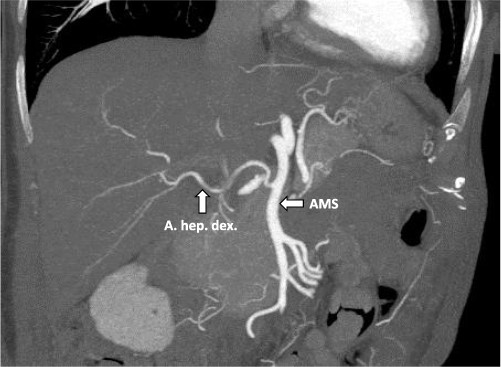

After multidisciplinary tumor board (MDT) discussion, neoadjuvant chemotherapy with six cycles of FOLFOXIRI and Bevacizumab followed by liver-first approach was decided. Restaging after 3 months showed stable disease of the CRLM, therefore, chemotherapy was continued. After 12 cycles, restaging revealed a size reduction of 12% of the CRLM (Fig. 1B). CEA decreased from 69 to 6.1 ug/l. The patient was then admitted to our department for the evaluation of a curative intent CRLM resection. The radiological work-up revealed three remaining metastases on the left- and seven on the right hemiliver. Volumetry illustrated a standardized FLR (sFLR) for a right hemihepatectomy of 30%. In an MDT and the patient was deemed amenable to ALPPS surgery due to the marginal sFLR, bilobar metastases and exceptionally good performance status. Preoperative liver function tests showed normal liver function (LiMAx 450 mcg/kg/h, cut-off >315 mcg/kg/h and ICG R15: 4.0%, cutoff <12%). Although liver biopsy is not routinely performed before ALPPS, MDT recommended a biopsy of the healthy liver to rule out chemotherapy-associated steatohepatitis after 12 cycles of FOLFOXIRI and Bevacizumab in order to ensure a safe liver resection. The biopsy showed signs of subacute hepatocyte demise without fibrosis or cirrhosis. The day after the liver biopsy, the patient collapsed and was admitted to the emergency department of another hospital. CT scan showed a large intrahepatic hematoma (Fig. 2) without active bleeding probably secondary to the biopsy procedure. Due to a hemoglobin drop of 12 g/l a day later and the enlargement of the hematoma in follow-up CT scan, the patient was admitted to angiography, which showed several subcapsular liver bleedings, therefore the right hepatic artery was embolized. Luckily, an accessory right hepatic artery arising from the superior mesenteric artery was present. This enabled us to stay on track with the ALPPS procedure as the right hemiliver would be otherwise without any blood supply (Fig. 3). In synopsis of those findings, the operation was scheduled.

CT-angiography showing the accessory right hepatic artery originating from the superior mesenteric artery.